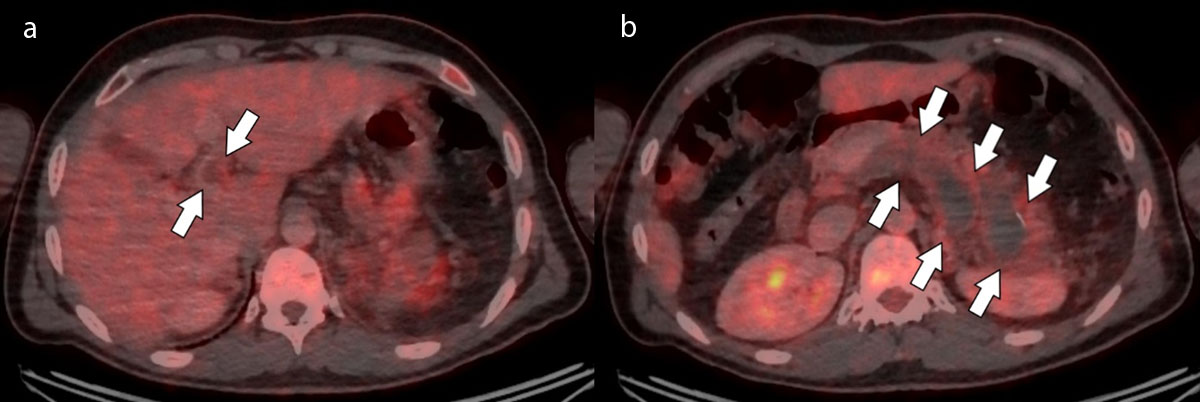

Figure 2

Axial FDG-PET/CT slices at the level of the splenic vein (Figure 2a) and portal vein (Figure 2b) showing absence of metabolism within the thrombus and some hypermetabolic infiltration of surrounding fat (arrows).